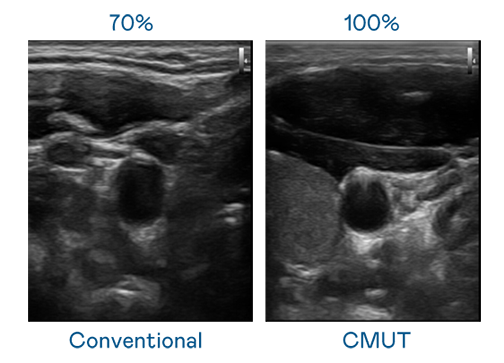

CMUT 技术是一种用电容式微机电元件来产生超音波讯号的技术。与传统 PZT 压电式技术相比,CMUT 频宽增加 30%,更宽频的超音波讯号让影像解析度大幅提升,是实现高影像品质医疗超音波扫描、促进精准医疗发展的关键技术。

大频宽带来超清晰影像

超音波影像的解析度高低,首先取决于探头能发出的讯号频宽。银钻国际 CMUT 可提供高清晰的超音波讯号,提供高频宽、高灵敏度、影像纹理细节更高的超音波影像,协助医护人员缩短影像判读时间及利用精准的医疗影像进行诊断。